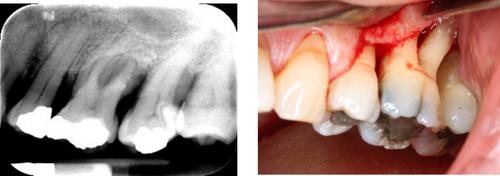

A member of the public served as a co-investigator. Twenty participants with at least one grade III furcation-involved molar tooth were randomized to either non-surgical periodontal treatment (NSPT) or open-flap debridement (OFD). They were reassessed 6 months later, where ‘successful response’ to therapy was defined with a ‘combined outcome’ incorporating patient-reported and clinical parameters. Based on SMART principles, non-responders underwent further treatment and were followed up to 12 months.

All study feasibility criteria were met, except ‘planned recruitment rate’, which was slower than expected. At the 6-month review, those who underwent OFD showed a greater reduction in probing pocket depth (PPD) compared to those who received NSPT (p = < 0.01). ‘Success’ was reached by 6 out of 10 NSPT participants and by 7 out of 10 OFD participants. Non-responders were further randomized and followed up to 12 months.